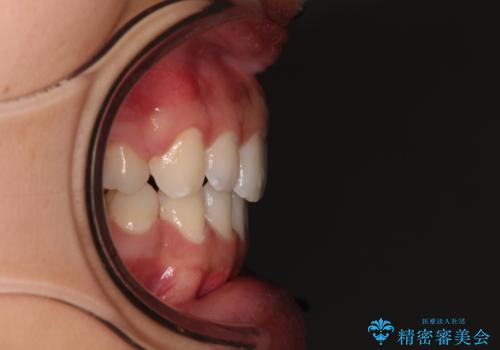

- 出っ歯で唇が閉じにくいとのことで来院された患者様です。

顎先に力を入れないと唇が閉じきれない口元であったので、上下左右の第一小臼歯4本を抜歯して、ワイヤー装置にて矯正治療を行うこととしました。